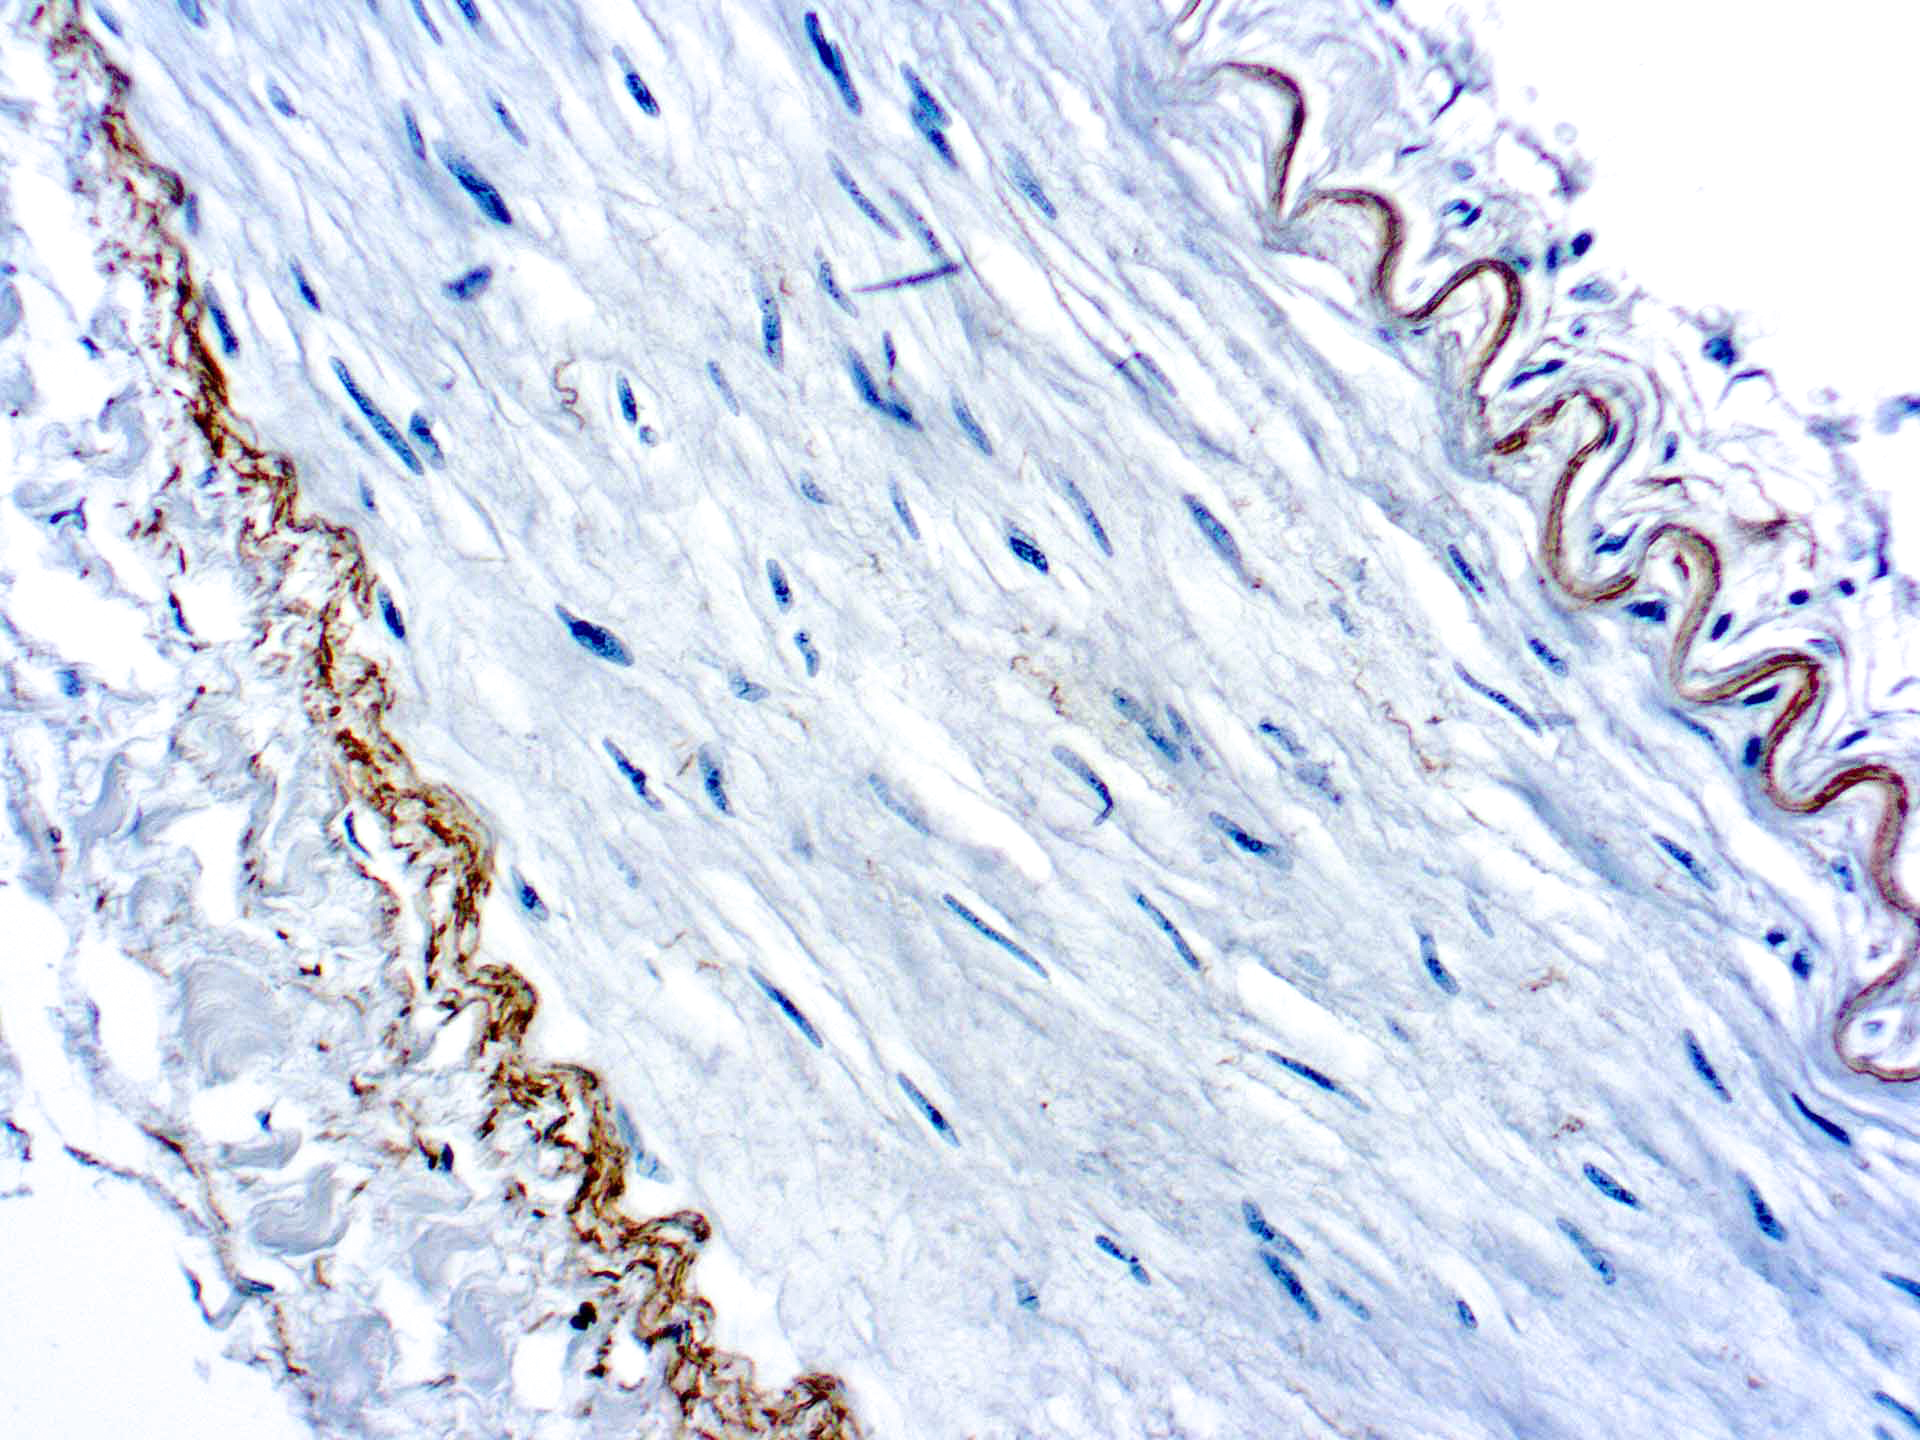

This antibody recognizes insoluble elastin, α-elastin, soluble non-cross linked precursor of elastin (tropoelastin). Elastin is an important polymeric protein of connective tissue that imparts elasticity to vertebrate elastic tissues.

| Cellular Localization | Connective tissue |

| Positive Control Tissue | Heart, Kidney |